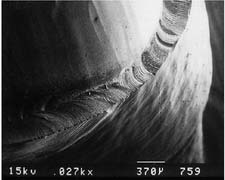

The junction between a cemented restoration and the tooth is always a potential site for recurrent caries because of dissolution of the luting agent and inherent roughness. The more accurately the restoration is adapted to the tooth, the lesser is the chance of recurrent caries or periodontal disease.32 Although a precise calculation for acceptable margin adaptation is not available, a skilled technician can routinely make castings that fit to within 10 μm33 and a porcelain margin that fits to within 50 μm,34 provided the tooth is properly prepared. A well-designed preparation has a smooth and even margin. Rough, irregular, or “stepped” junctions greatly increase overall margin length and substantially reduce the adaptation accuracy of the restoration (Fig. 7-18). The clinical significance of preparing smooth margins cannot be overemphasized. Time spent obtaining a smooth margin makes the subsequent steps of tissue displacement, impression making, die formation, waxing, and finishing much easier and ultimately results in a longer-lasting restoration.

The cross-sectional configuration of the margin has been the subject of much analysis and debate.35-42 Different shapes have been described and advocated.43,44 For evaluation, the following guidelines for margin design should be considered:

Fig. 7-19 Margin designs. A, Feather edge. B, Chisel. C, Chamfer. D, Bevel. E, Shoulder. F, Sloped shoulder. G, Beveled shoulder. H to M, Scanning electron micrographs. H, Feather-chisel edge. I, Bevel. J, Chamfer. K, Shoulder. L, Sloped shoulder. M, Beveled shoulder.

(Courtesy of Dr. H. Lin.)

Under most circumstances, feather edges and chisel edges are unacceptable. Historically, their main advantage was that they facilitated impression making with rigid modeling compound in copper bands (a technique rarely used today). They were useful for that purpose, because there was no ledge on which a band could catch. A chamfer margin (Fig. 7-19C) is particularly suitable for cast metal crowns and the metal-only portion of metal-ceramic crowns (Fig. 7-20). It is distinct and easily identified, and it provides room for adequate bulk of material and development of anatomically correct axial contours. Chamfers can be placed expediently and with precision, although care is needed to avoid leaving a ledge of unsupported enamel.